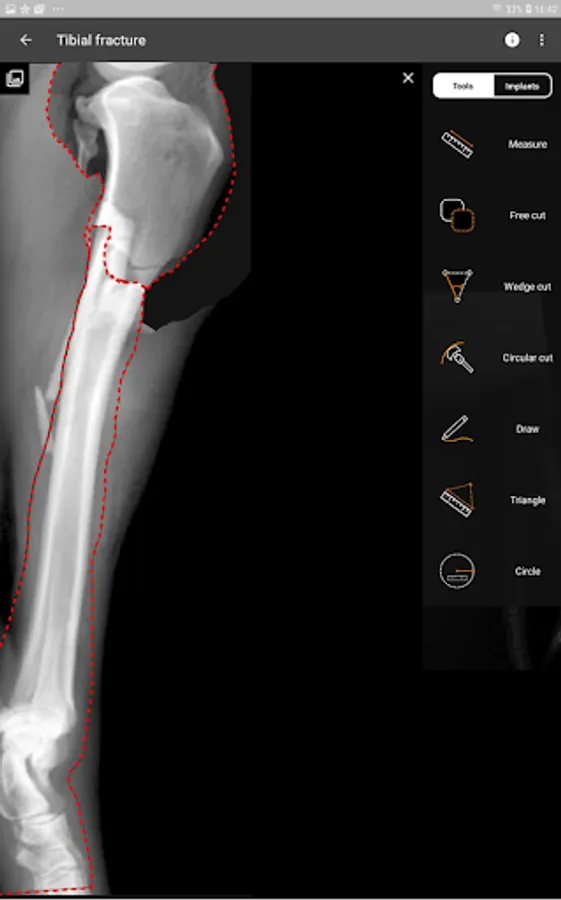

This is a useful tool for traumatology and orthopaedic surgical planning veterinary, including advanced techniques for treat canine anterior cruciate ligament (ACL) injuries (TPLO and CTWO).

3. Tools:

d) Free cut.

e) Wedge cut, CTWO and angular osteotomies.

f) Circular cut, TPLO.